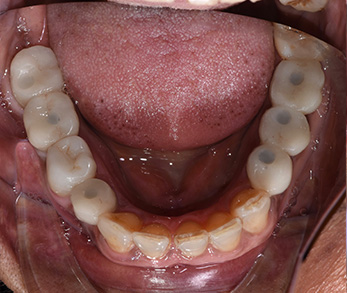

Ceramic Crowns

Cosmetic Dental Office Amityville

Before

Amityville Cosmetic Dentist

After